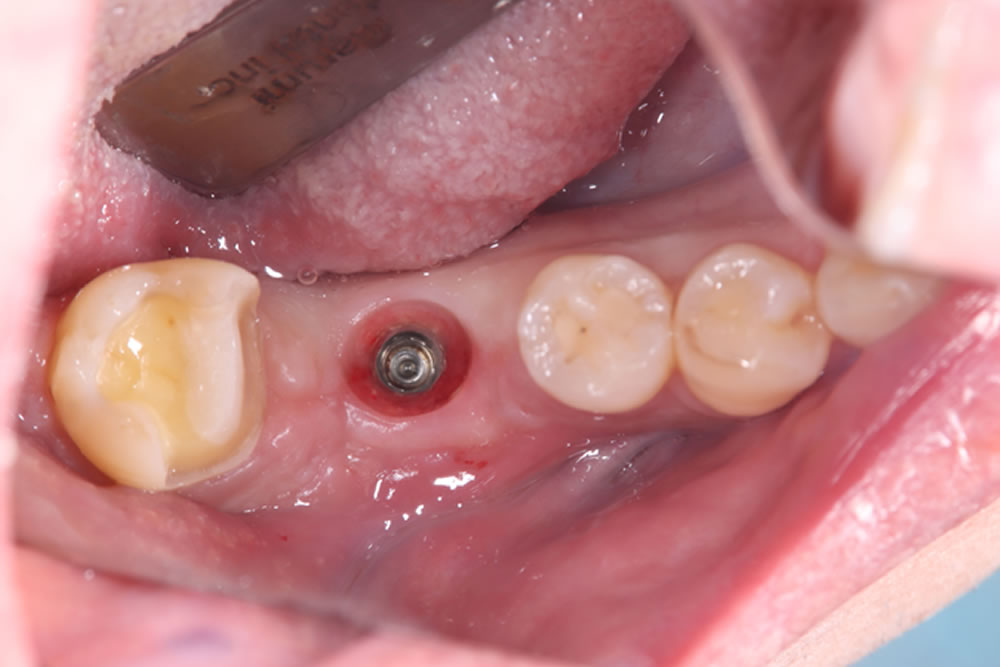

下顎に埋入したインプラントにプロビジョナル(精密仮歯)装着しました。